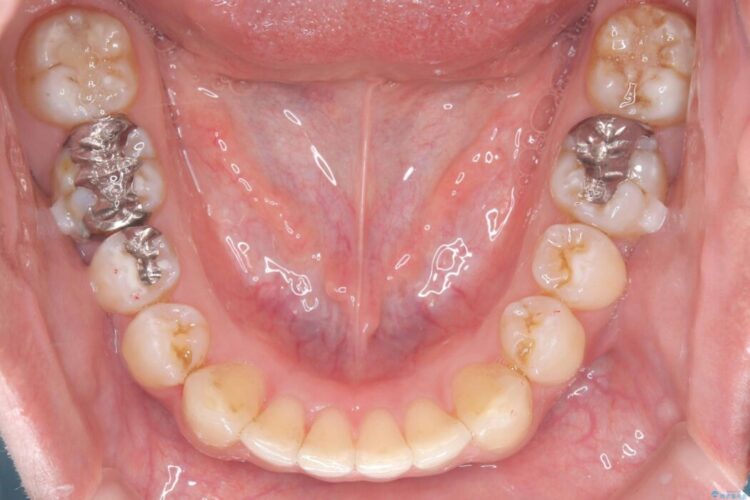

正中離開・叢生のほかに、上下の奥歯が全く咬み合わないシザーズバイトの状態も認められました。

歯の隙間とデコボコ、シザーズバイトも改善され、咬み合わせや見た目が整い、患者様にも大変ご満足いただけました。